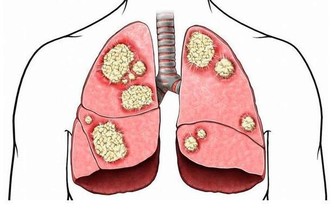

最終昏迷,一般死於感染等並發症。